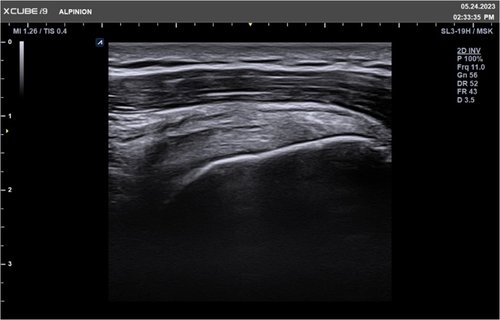

• SL3-19H (3-19 MHz) für Ultraschalluntersuchungen in Bereichen MSK, Vaskulär, Weichteile, Pädiatrie, EM

Für das X-CUBE i9 steht ein umfangreiches Schallkopfportfolio zur Verfügung. Somit kann das komplette internistische Spektrum inklusive der Kardiologie, aber auch Untersuchungen des Bewegungsapparates mit hochauflösenden Schallköpfen bis 25 MHz oder gynäkologische bzw. urologische Untersuchungen mit der Qualität eines Standsystems durchgeführt werden.

• MSK / Bewegungsapparat

Herausragende Bildqualität für vielseitige Diagnostik

Klare Bilder bieten Komfort und Sicherheit bei der Diagnose eines breiten Spektrums von Patienten.

Das X-CUBE i9 ist mit der X + Architektur, innovativen Bildgebungsalgorithmen und einem effizienten Diagnose-Workflow ausgestattet, um die vielfältigen klinischen Anforderungen mit kristallklarer Bildqualität effektiv zu unterstützen.